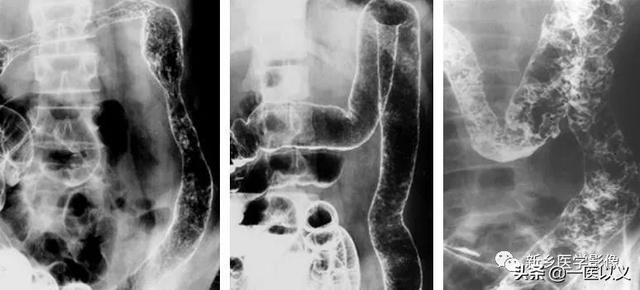

一方、バリウム注腸は中等度から進行性の潰瘍性大腸炎患者の診断に重要な役割を果たしている。腸粘膜の浮腫や潰瘍が認められる。

潰瘍性大腸炎の診断基準:①桿菌性赤痢、アメーバ性大腸炎、住血吸虫症、腸結核、クローン病、放射線性腸炎およびその他の大腸の炎症の原因を除外する、②典型的な臨床像があり、少なくとも内視鏡検査またはX線検査で1の特徴的な変化が認められる、③臨床症状は典型的ではないが、典型的な大腸内視鏡検査またはX線検査、あるいは生検による病理学的検査が行われ、潰瘍性大腸炎であることを確認できる